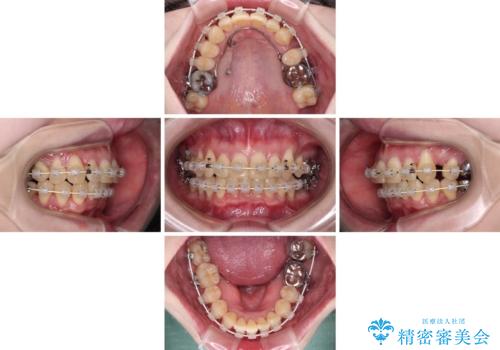

- 八重歯と正中のズレを気にして来院された患者様です。

上顎左側が八重歯になっており、上顎正中が左側にずれていました。

上顎左側の第一小臼歯を抜歯し、補助装置を用いて正中位置を改善しながら八重歯を解消していくこととしました。

下顎前歯が1本欠損していたため、上下正中の位置が合わせるという目標はなく、鼻筋に上顎正中を合わせていくように移動を行いました。